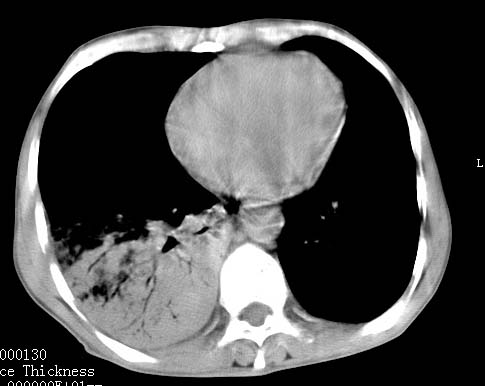

病人女 60岁 咳嗽 气促十余天,大叶性肺炎.

右肺上下叶均见 大片状密度增高影,边界清晰,其内可见支气管充气征,气管支气管通畅。纵膈略向右移位,其内无肿大淋巴结影。首先考虑炎性病变。不排除一些特异性的炎症。不知道发烧吗??wbc高吗??建议治疗后复查!!